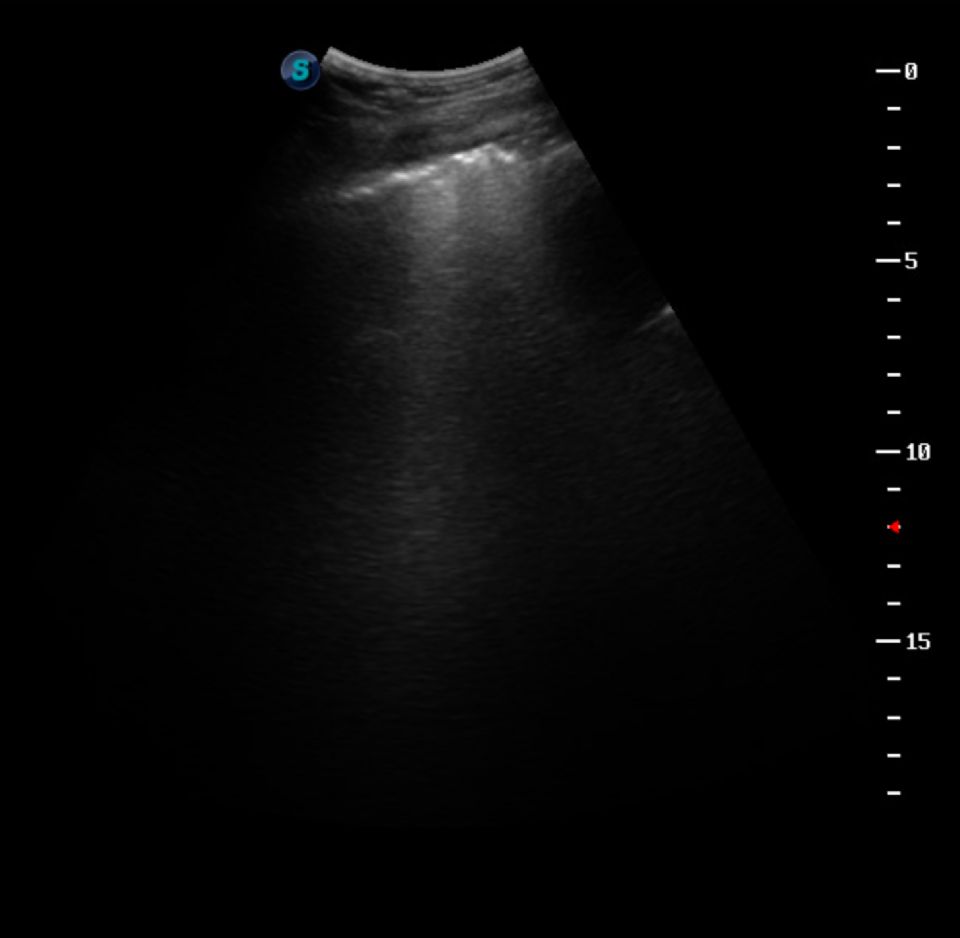

Dr. Berzas performed a thoracic ultrasound and spotted comet tails in her lungs, leading to one thing: pneumonia.

“We were wracking our brains to figure out what the original stressor might have been that led to the hyperlipemia, but Madi did not display any signs of pneumonia at the clinic and did not cough once,” said Dr. Berzas. "Then, there it was! Donkeys are stoic, tough animals, and sometimes they don’t give us traditional clinical signs.”